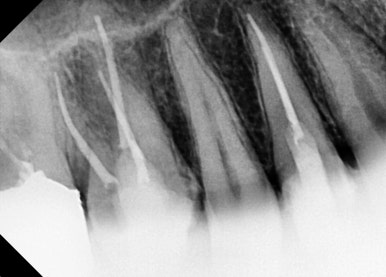

📸 케이스 1: #37 C-shape Re-Endo

- 통증 및 치아 흔들림 호소

- C-shape 근관 구조로 난이도 높은 케이스

- 여러 차례 소독 및 MTA 실러로 근관 충전

✅ 1년 후까지 안정적인 상태 유지